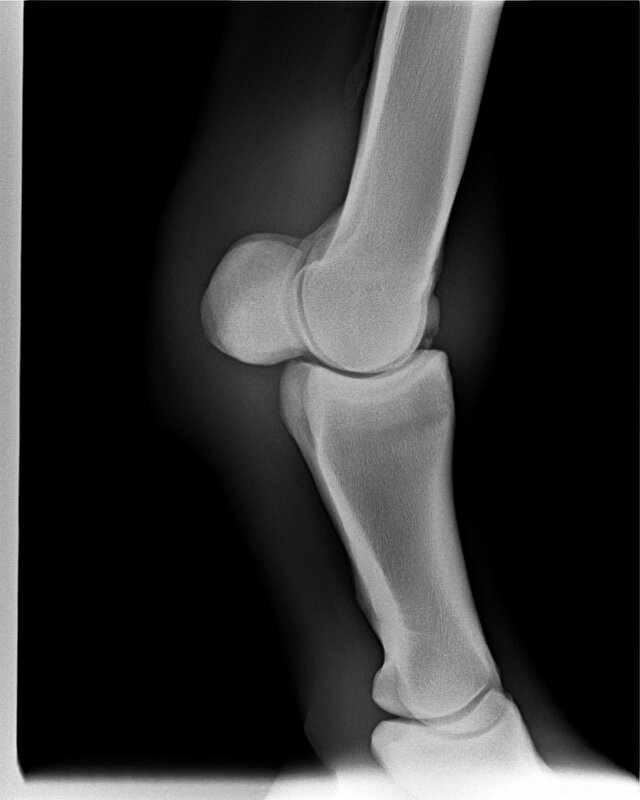

Mijn paard had ook al wat schade in het gewricht. Gedurende de operatie (mijn dochter was erbij) leek dat best groot gezien de krassen die te zien waren) maar in de praktijk viel dat reuze mee. Tijdens de operatie is dat via de camera natuurlijk erg uitvergroot. De chip was ook maar klein. Normaal gesproken, bij een chipoperatie, nemen ze middels een kijkoperatie het chipje weg (arthrectomie). Dit is een vrij standaard en simpele operatie. Paarden zijn dan ook weer snel op de been. Inderdaad met een week of 6 is het dan wel klaar. Mijn paard loopt dermate goed, dat een PRP behandeling niet nodig was.

Ik heb de indruk dat het botfragment bij het paard van TS dus vrij groot was. Gezien men ook het bot heeft moeten vlakken. Dan is de schade in het gewricht ook groter. Mogelijk zo groot dat geen herstel meer mogelijk is. Hoe lang je het paard ook rust geeft. Ik kan me niet precies visualiseren hoe het bij haar paard precies zit, maar dit is wat ik ervan weet.